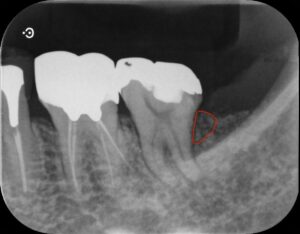

赤い線で囲んである部分が処置したところです。

処置後9ヶ月ほど経過して安定しております。歯茎の腫れもなくなり、揺れも治ってきています。

これだけ骨の吸収が大きいと抜歯を余儀なくされることも多いですが、今回は残していけそうです。